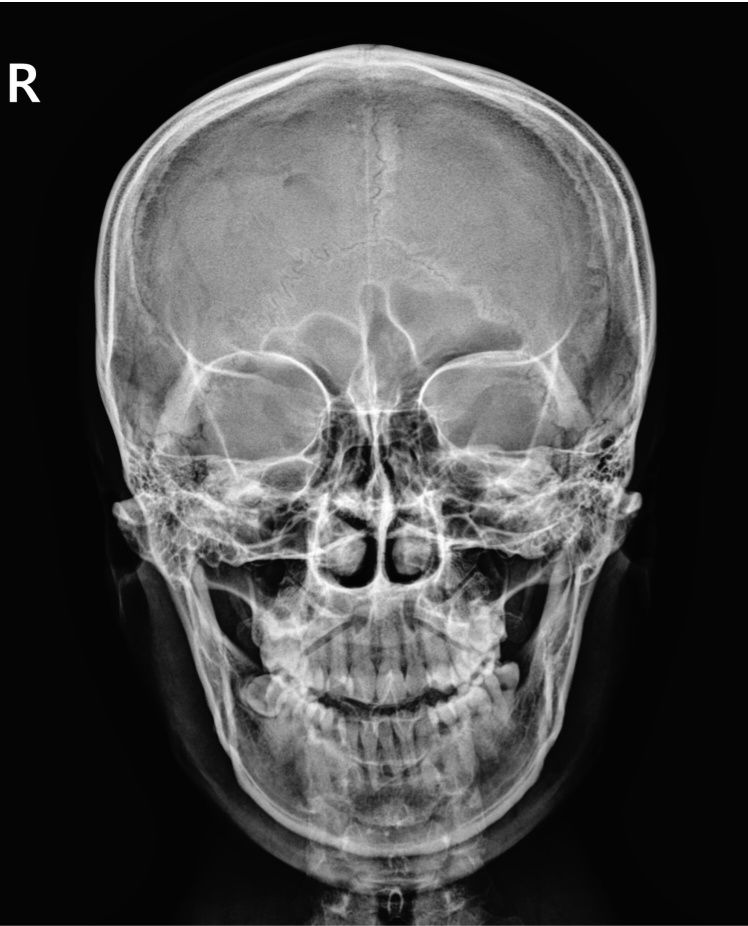

제 두개골 x레이인데요

첫번째 사진은 상악동이 넓고 오른쪽 사진은 좁아졌잖아요

눈과 상악동 사이에 있는 접형골? 이 밑으로 내려왔잖아요

병원에서는 각도차이로 그렇게 보이는거라고 하는데 전 뼈 위치가 물리적으로 바뀐거 같아요

엑스레이 각도 차이로 보이는 차이가 흔하고 실제 뼈 위치가 크게 변하는 경우는 드뭅니다. 접형골은 두개골 깊숙한 곳에 있어 쉽게 움직이지 않아요 정확한 평가를 위해 촬영이나 전문의 상담이 필요합니다! 심각한 변위가 확인되면 치료 가능하지만 대부분은 자연 상태 유지가 일반적입니다!

• 우선 외상이 아니라면 접형골이 밑으로 내려오는 경우는 없으니 걱정하지 마세요

그리고 사진을 찍은 각도가 차이가 납니다.

두 번째 사진의 경우 첫번째에 비해서 고개를 약간 숙인 상태로 찍어서 상악동이

상대적으로 찌그러져 나온 것입니다.